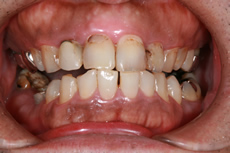

術前